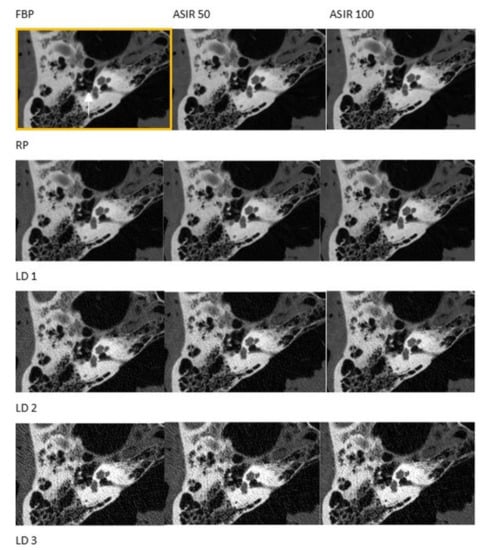

| FBP/Kernel | FBP/BONE2 |

| IRT/Kernel | ASIR 50/BONE2 |

| IRT/Kernel | ASIR 100/BONE2 |